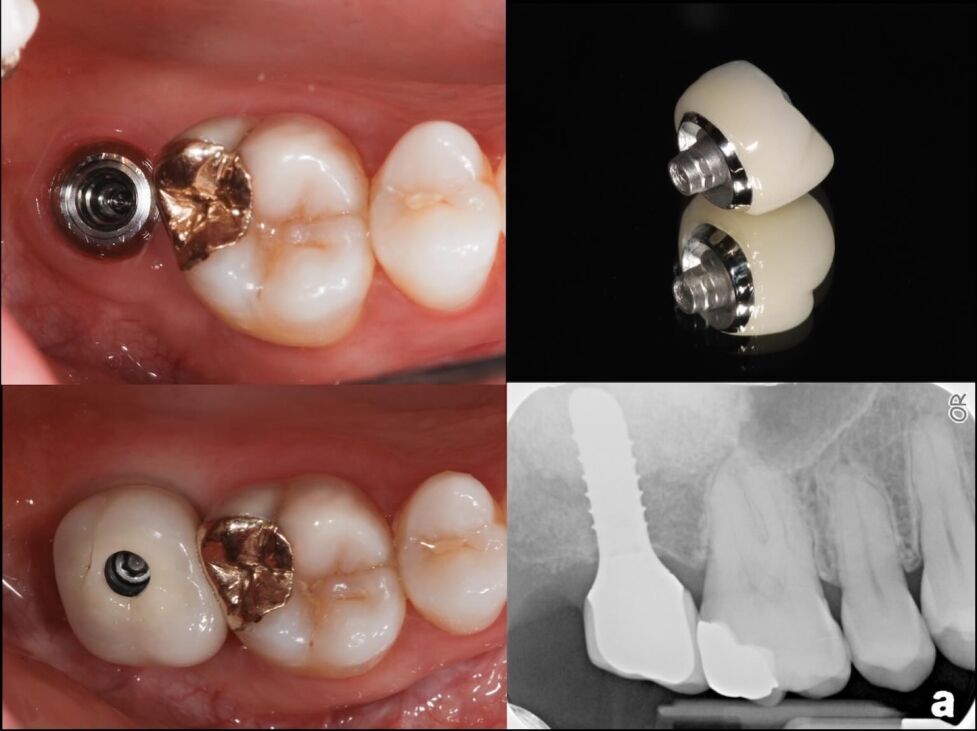

Restoring single tooth implants with the Straumann Implant system

Restoring Single Tooth Dental Implants